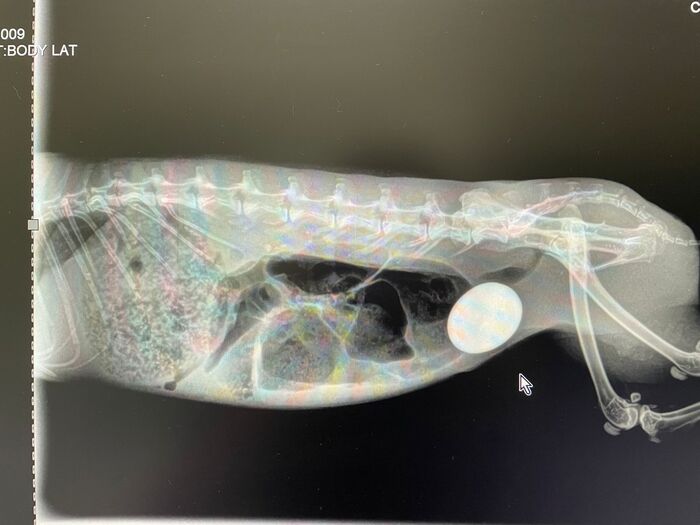

Piedras riñones / vejiga

Este es el caso de un conejito que sufría de colapso en la vejiga, como podréis ver en las radiografías tiene una cálculo enorme que le ocupa la vejiga entera, esto le producía un gran dolor y la imposibilidad de orinar, por lo que los riñones sufrían riesgo de colapso en cualquier momento. Tenía graves problemas digestivos también causados por dolor y por una parálisis en el intestino (íleo paralítico), algo que es muy grave en conejos, no podía digerir bien la comida y dejó de comer, antes de ello tuvo diarrea un tiempo.